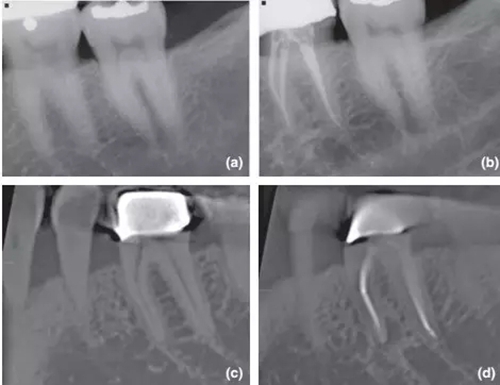

36術(shù)前X片,無根尖暗影;

1年回訪X片,根尖周無異常,診斷為成功的根管治療;

CBCT對(duì)同一個(gè)36進(jìn)行術(shù)前掃描,無根尖暗影;

1年回訪使用CBCT,發(fā)現(xiàn)新出現(xiàn)的根尖暗影,診斷為和X片完全相反的根管治療失敗。

CBCT掃描不受解剖噪點(diǎn)影響,對(duì)根尖周組織還原度高,而且還能做出精確的線性和容積測(cè)量,這些特點(diǎn)都十分有利于對(duì)骨損愈合的監(jiān)控。其中最具影響力的文獻(xiàn)當(dāng)屬由 Patel 在2012年發(fā)表的根管治療術(shù)后1年回訪臨床實(shí)驗(yàn),是第一篇應(yīng)用CBCT進(jìn)行術(shù)前及術(shù)后后掃描比較的研究。